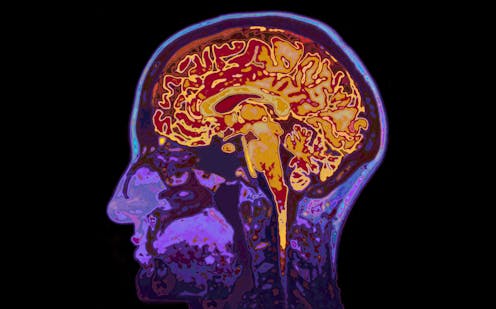

We are researchers with the world-first Longitudinal Adolescent Brain Study (LABS). We have been tracking adolescent brain development, using MRI scans, for several years. Our recent paper is the first to show the uniqueness of an adolescent’s brain (or their “brain fingerprint”) can predict mental health outcomes.

To date, our study involves 125 participants, from 12 years of age, with over 500 brain scans among them. Our research captures brain and mental health development in adolescents over five years. It uses four-monthly brain imaging (MRI and EEG), and psychological and cognitive assessments.

The MRI scans were undertaken during a resting state, as opposed to task-based functional MRI. It still tells us a lot about brain activity, such as how the brain keeps connections running or gets ready to do something. You could compare this to a mechanic, listening to a engine idling before it’s taken for a drive.